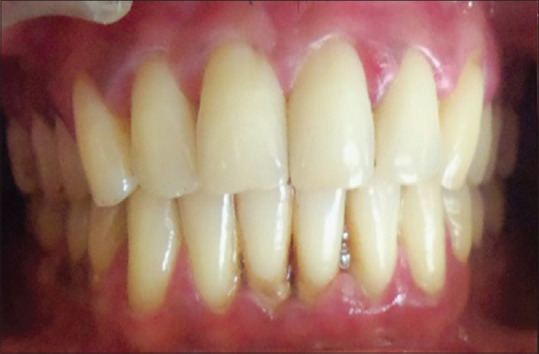

Materials and methods: A study included 100 subjects divided into four groups. Group I: stable coronary artery disease with chronic periodontitis, Group II: stable coronary artery disease without chronic periodontitis, Group III: chronic periodontitis without coronary artery disease, and Group IV: healthy controls. Gingival index, Russell's periodontal index, pocket depth, and clinical attachment level were recorded. Venous blood was collected from the patients, and serum fibrinogen, CRP, and lipid profile levels were estimated.